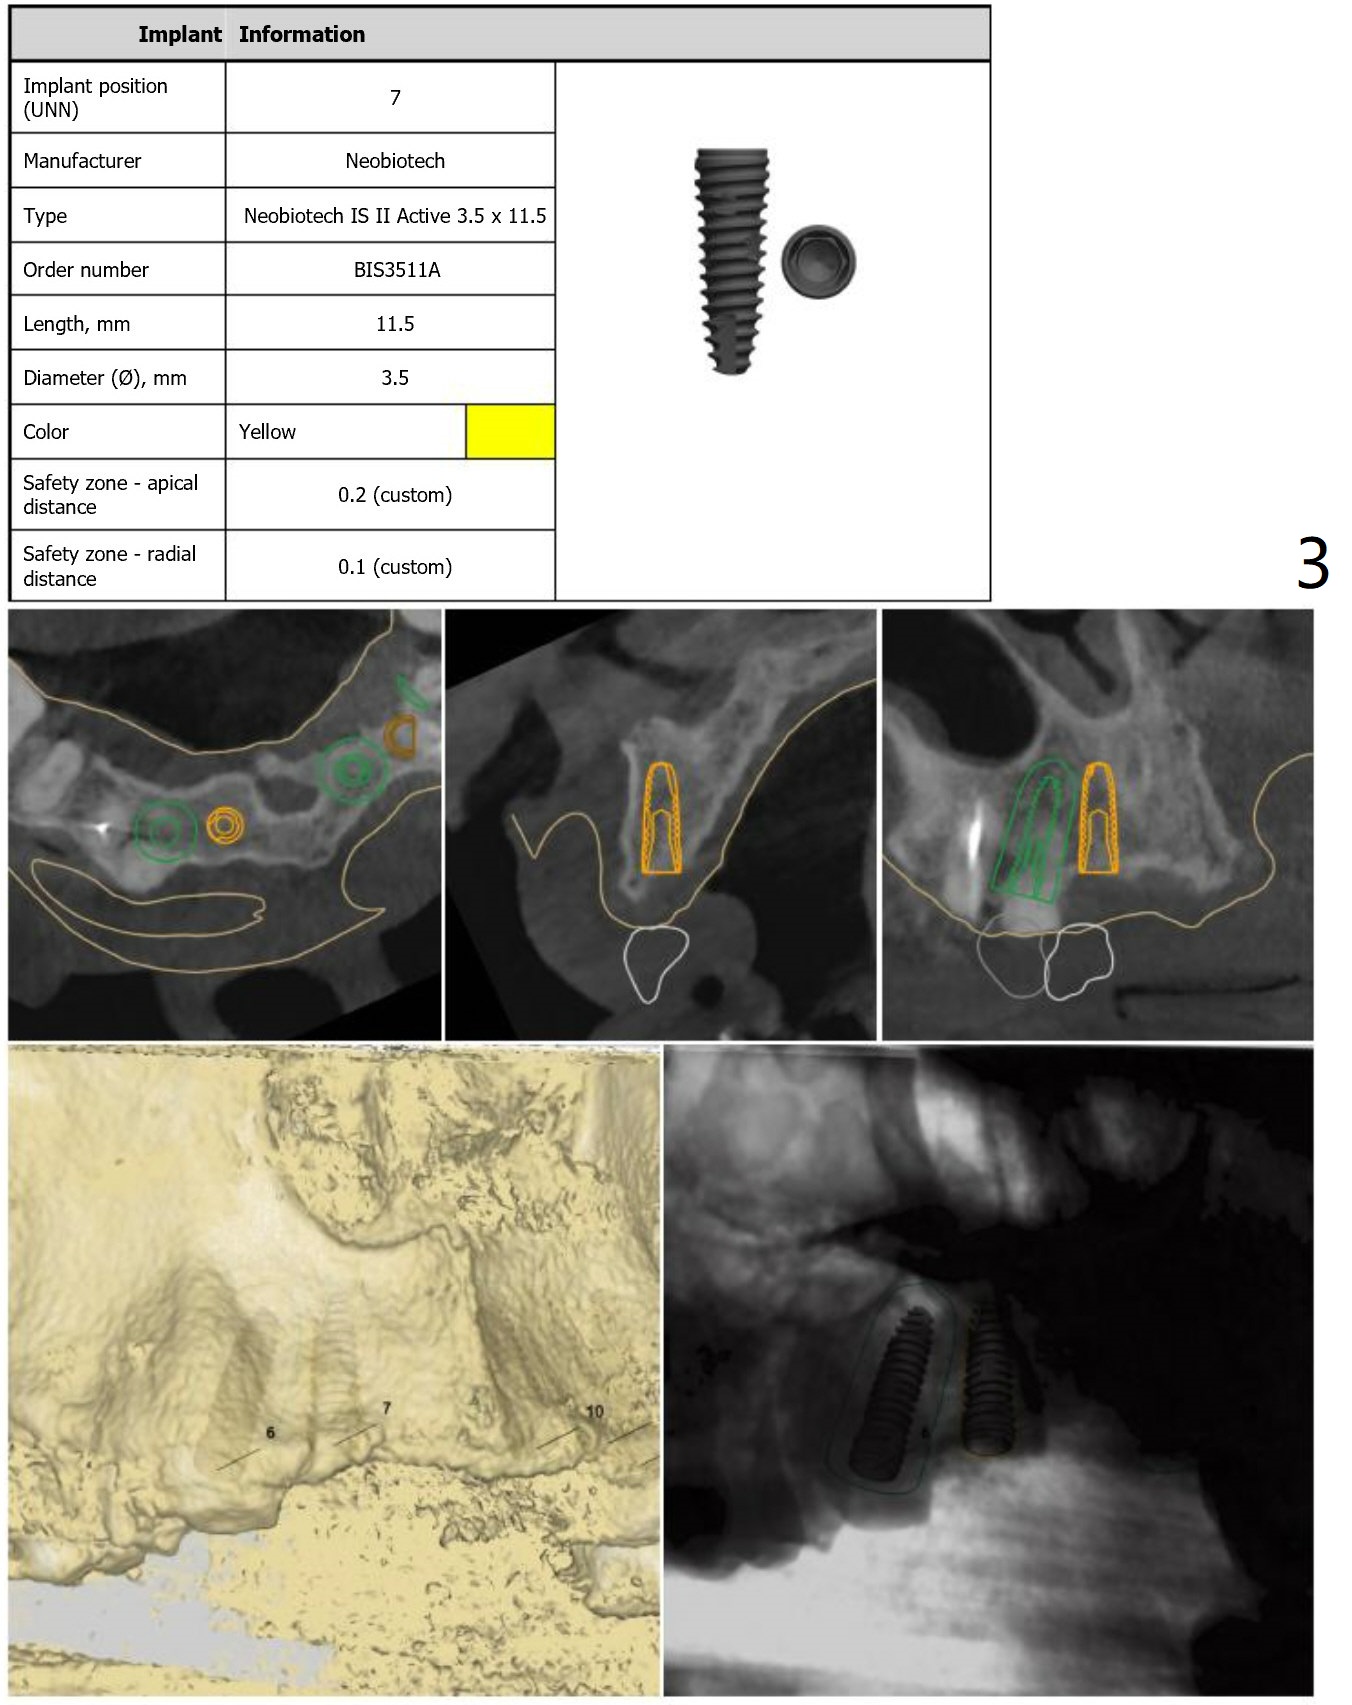

Since the apex of the tooth #5 seems to tilt mesial, implants at #6 and 7 will be placed mesial intentionally with diameters of 3.5 and 3 mm (Fig.1-3). On the left side with minor space issue, two-piece implants with 3.5 mm in diameter will be placed at #11-12 (Fig.5-6). After implant osteointegration, a 4-unit FPD will be fabricated between #7-10. Return to Upper Arch Immediate Implant, Trajectory, Metronidazole Xin Wei, DDS, PhD, MS 1st edition 11/09/2018, last revision 11/16/2018